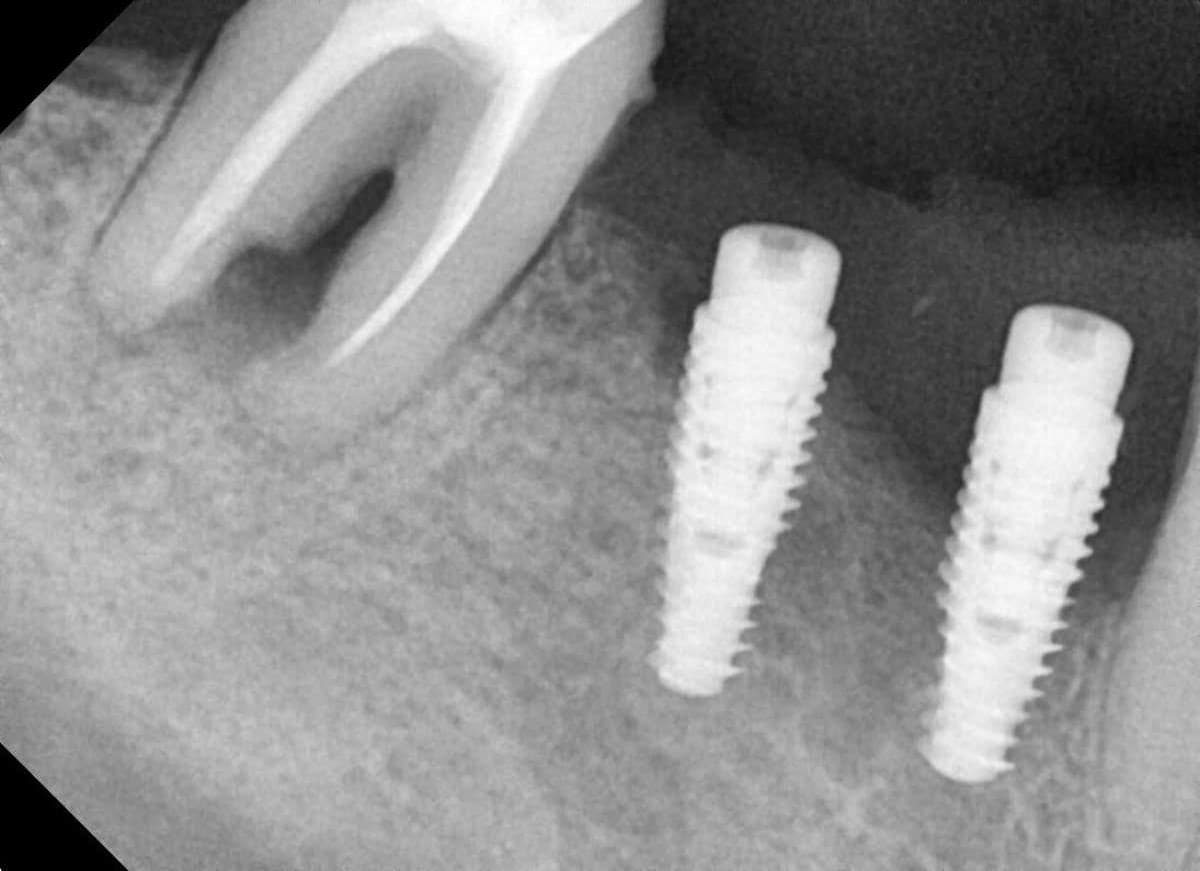

¿Te acaban de colocar un implante dental o quizá estás pensando colocarte uno?

Descubre aquí todos los cuidados que debes tener.

Que los implantes dentales sean de titanio no quiere decir que sean a prueba de todo. Por el contrario, al igual que los dientes, los

En este artículo de Clínica de Encías, hablaremos sobre cómo reconocer los síntomas de un posible rechazo de implante dental. Es importante estar atentos a

¡Bienvenidos a Clínica de Encías! En este artículo hablaremos sobre la importancia del control en los implantes dentales. Es fundamental realizar revisiones periódicas para asegurarnos

Los implantes dentales son una excelente opción para reponer piezas dentales perdidas, pero también pueden infectarse. En este artículo hablaremos sobre las causas, síntomas y

En este artículo hablaré sobre las contraindicaciones que pueden surgir en la colocación de un implante dental. Es importante conocer los factores de riesgo que